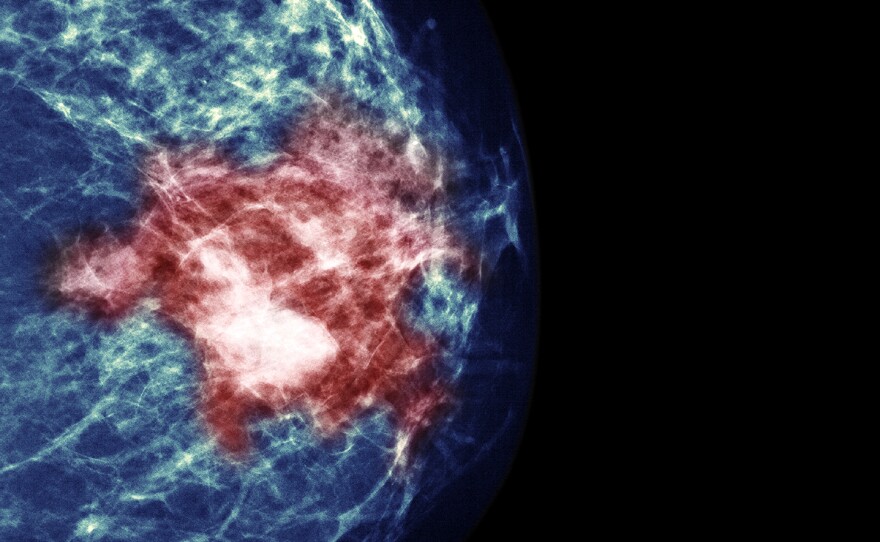

By testing tumors, researchers hoped to identify women who could avoid chemotherapy without increasing their risk of a cancer recurrence.

Voisin/Phanie Science Source